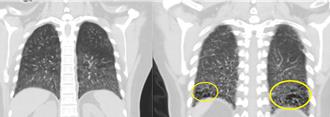

33歲男星久咳不癒「確診第4期肺腺癌」 打標靶被迫停工

33歲香港男演員柯煒林,曾拍過《點五步》、《破浪男女》等,更以電影《濁水漂流》提名金馬獎及香港電影金像獎最佳男配角。今(30日)他無預警宣布罹患肺腺癌第四期,震撼外界。

不抽菸、沒不適 男健檢竟肺腺癌4期 月花20萬續命

肺癌是國人最好發的癌症,胸腔內科醫師蘇一峰分享一名中年男子,沒有抽菸無不適,因健檢看到X光有點問題,由他診斷是肺腺癌第4期,男子月花20萬使用自費標靶藥物,至今已燒掉上百萬元,讓蘇一峰感嘆健保花200億元在肺癌,其實有更多病人是自費在治療,「人活多久就要買多久的藥」。

獨家》不菸不咳!19歲女大生車禍急診 竟抓出肺腺癌

肺癌是國人最好發的癌症,逾6成病例等到出現久咳不癒、疲倦或體重減輕等症狀才就醫,此時病程多已屆晚期,以第4期而言,5年存活率僅1成5,高雄長庚醫院胸腔外科醫師陳聿表示,低劑量電腦斷層檢查可發現早期肺癌,提升存活率,該院曾收治1名19歲女大生,因此發現1期肺腺癌,術後恢復良好。